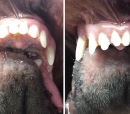

Oh My, is that a tongue that I see hanging out of Chance's Mouth?  Why yes it is.   Our sweet boy can open his mouth a little over an inch and a half comfortably.  He is still adapting to a bit of discomfort in the jaw area but is doing great.  He can eat soft food without any issues and is playing with kibble at this point.

Sweet does not begin to describe this fantastic dog. Chance is gentle and kind to every animal and person he meets.  All he wants to do is give kisses which is something he was not able to do before.   He can also cool himself by panting which was a significant problem he was having before the surgery.  Dogs pant to cool their core body temperature. Your body will over-heat without this ability during hot summer months.  Chance was found as a stray during the hottest days of summer.